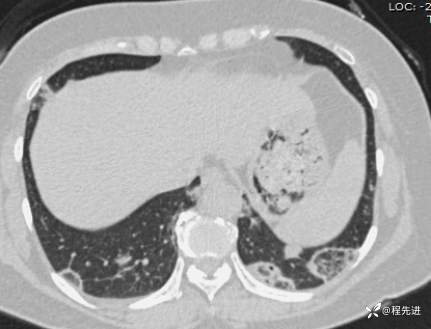

【心胸】特别精彩病例|胸闷1月余,好漂亮的反晕征呀

患者性别:女

患者年龄:57岁

简要病史:胸闷1月余

抗中性粒细胞胞质抗体相关性血管炎 (15)